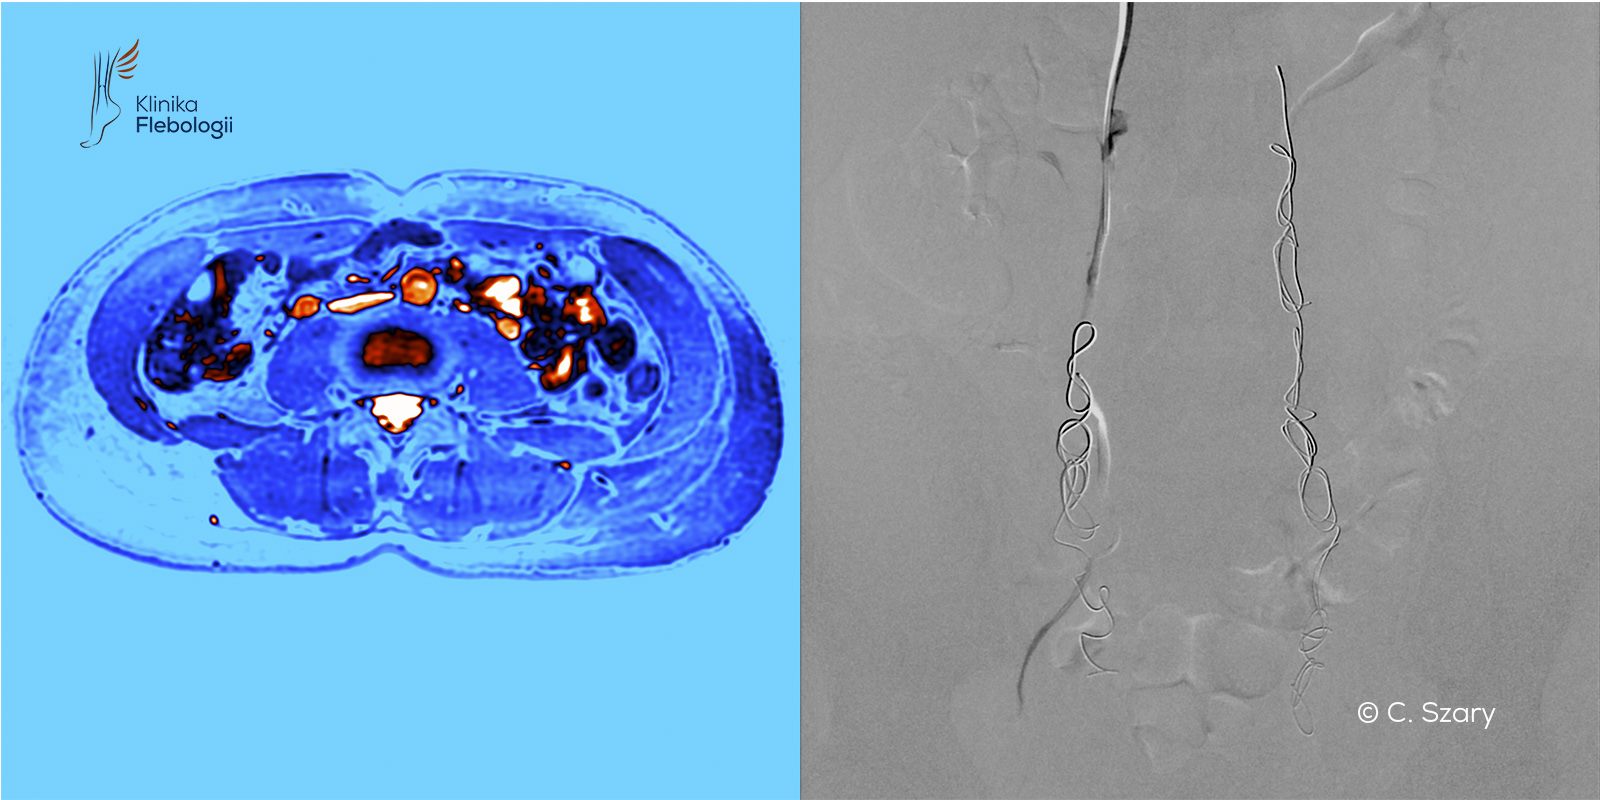

Decyzja i planowanie ewentualnego zabiegu poprzedzane są wykonaniem dokładniejszych badań obrazowych, takich jak wenografia MR lub TK. W zespole Kliniki Flebologii zajmują się tym specjalnie przeszkoleni radiolodzy: Michał Zawadzki i Cezary Szary.

W tym celu wykorzystywany jest najnowszy wysokopolowy rezonans magnetyczny firmy Philips (siła pola magnetycznego 3 Tesle), który poza obrazowaniem układu żylnego w MR umożliwia diagnostykę najczęstszych chorób, imitujących objawy zespołu przekrwienia żylnego miednicy, takich jak: endometrioza, adenomioza macicy, zapalenie narządów miednicy mniejszej czy zapalenia jelita.

W pracowni hemodynamiki Szpitala Medicover stosujemy zdecydowanie najczęściej zabiegi małoinwazyjne przeprowadzane drogą wewnątrznaczyniową. Każdy zabieg wykonywany jest pod kontrolą sondy USG i cyfrowej aparatury angiograficznej (tworzony jest tzw. venogram).